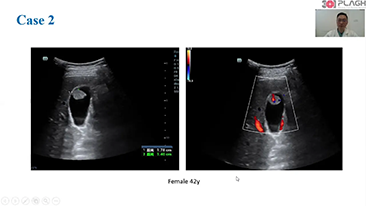

Kad?n sa?l??? tarama ziyaretlerinde yĂŒksek dĂŒzeyde hasta hacimlerini desteklemek i?in, optimize edilmi? OBG i? ak??lar? gerekir. ?rne?in, merkezi sinir sistemi (CNS) malformasyonlar?, en yayg?n g?rĂŒlen konjenital anormalliklerden biridir. K?tĂŒ fetĂŒs pozisyonu gibi, ?e?itli g?rĂŒntĂŒleme durumlar? nedeniyle, 2 boyutlu ultrasonda MSPâyi elde etmek ?zellikle zordur. Bu nedenle, otomatik alg?lama ve ?l?ĂŒmler, tarama verimlili?ini bĂŒyĂŒk ?l?ĂŒde art?rabilir.